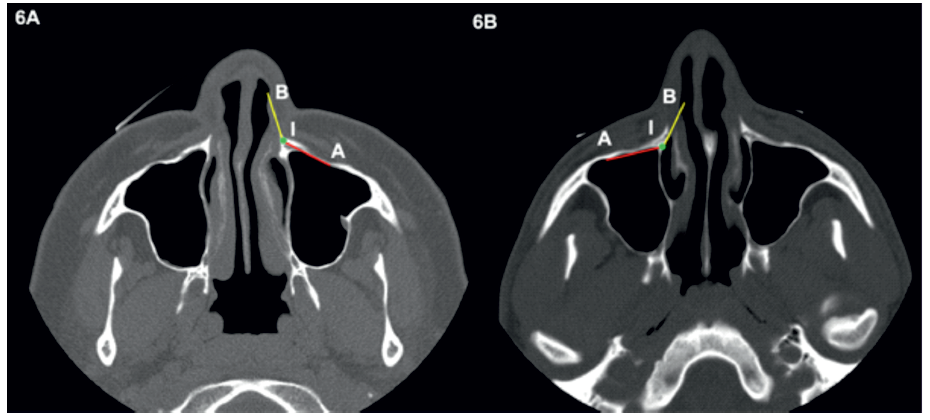

A posição do NAAS também foi avaliada. Foi seguido o seu trajeto a partir do canal infraorbitário até à apófise frontal da maxila. Uma vez nesta localização, este foi considerado estar numa posição vulnerável caso se encontrasse posteriormente à linha A e/ou medialmente à linha B (linhas A e B definidas anteriormente) (Figura 6).

Figura 6 Em (A) o nervo alveolar anterior superior encontra-se posteriormente à linha A, estando numa posição vulnerável. Em (B) o nervo alveolar anterior superior encontra-se anteriormente à linha A e lateralmente à linha B, estado numa posição não vulnerável.